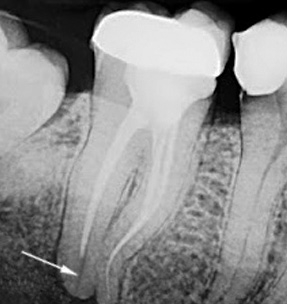

Um canal incompletamente selado: normalmente deve ser selado a um estreitamento fisiológico, ou seja, não atingindo o ápice radiológico visualmente determinado da raiz do dente em cerca de 1-2 mm. Independentemente do material escolhido, esse requisito deve atender ao protocolo de tratamento da pulpite. Caso contrário, ocorrerá inflamação da raiz.

Um canal excessivamente selado: ao remover uma grande quantidade de material de preenchimento além da raiz, o dentista corre o risco de dar ao paciente além de dor de dente severa após o tratamento da pulpite, também grandes problemas no futuro. O fato é que os padrões para o tratamento da pulpite proporcionam um preenchimento claro do canal de acordo com seu comprimento de trabalho, medido com uma régua, usando um dispositivo especial, raio-X etc. Quando o material atinge o ápice da raiz, é percebido como um corpo estranho, o que acarreta uma resposta e provoca inflamação dos tecidos ao redor da raiz.